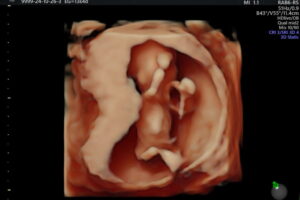

Galería de recuerdos felices Las primeras fotos de Ambar y la historia de sus papás-